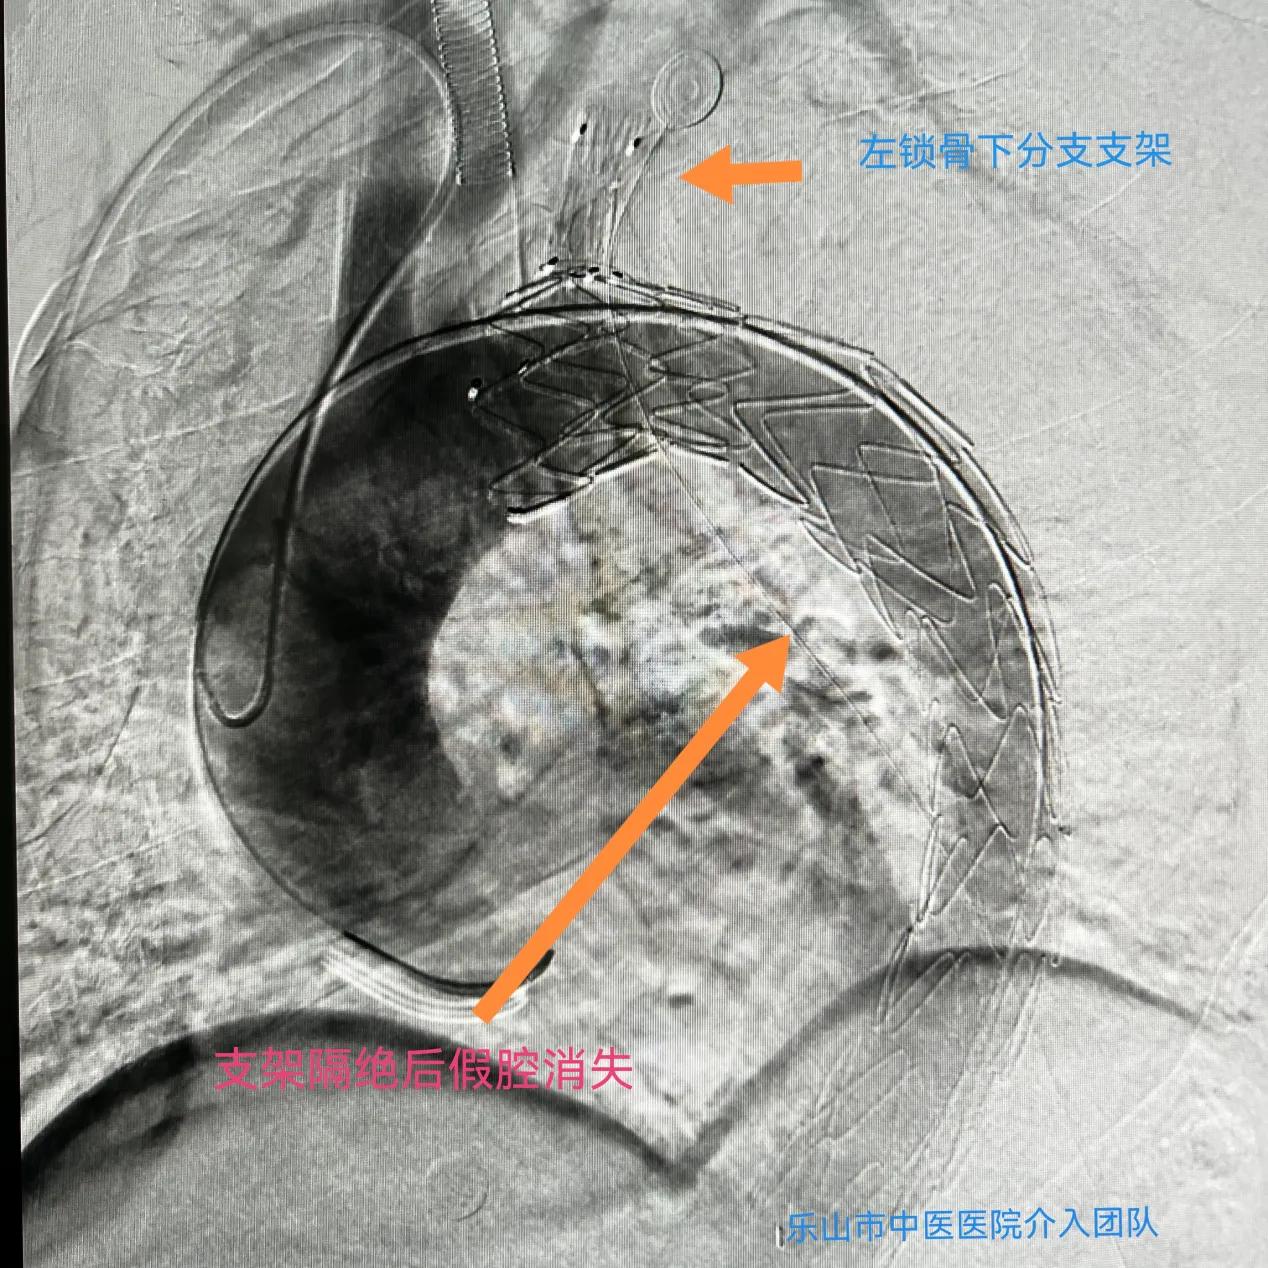

考虑到病人病情复杂,介入科团队决定分次进行手术,“先处理椎动脉夹层动脉瘤,待术后平稳后再行二期手术处理主动脉夹层动脉瘤”。10月15日,经周密术前准备,科室副主任刘先军带领医生团队,为患者成功行椎动脉血流导向装置pipeline置入,五天后再行分支型主动脉腹膜支架置入。术中各项指标稳定,目前患者已逐步康复。

“手术采用了目前最先进血流导向装置、分支型主动脉腹膜支架置入技术,这样的技术在同级医院内属领先”,刘先军副主任告诉记者,“而由同一手术团队完成头、胸两个部位血管的手术,这样的‘一站式服务’也避免了病人辗转奔波,缩短了病程,有助于患者的快速康复”。